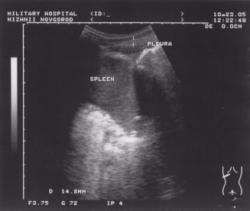

Рассмотрим еще один пример. Пациент В., 1988 года рождения. (рис2;3). Находился на лечении в пульмонологическом отделении госпиталя с диагнозом: двусторонний гломерулонефрит.

При проведении флюорографического исследования легкие расправлены. Легочная ткань без очаговых и инфильтративных изменений. Корни легких структурные. Диафрагма четко контурирована, синусы свободные. Органы средостения не изменены. Т.е. по данным рентгенографии абсолютная норма.

При проведении ультразвукового исследования в обеих плевральных полостях определяется наличие свободной жидкости толщиной слоя до 20 мм (объем около 200 мл). Структура жидкости однородная, анэхогенная. Реакция плевры отсутствует.

И в данном случае при проведении адекватной терапии основного заболевания плевральный выпот быстро регрессировал.